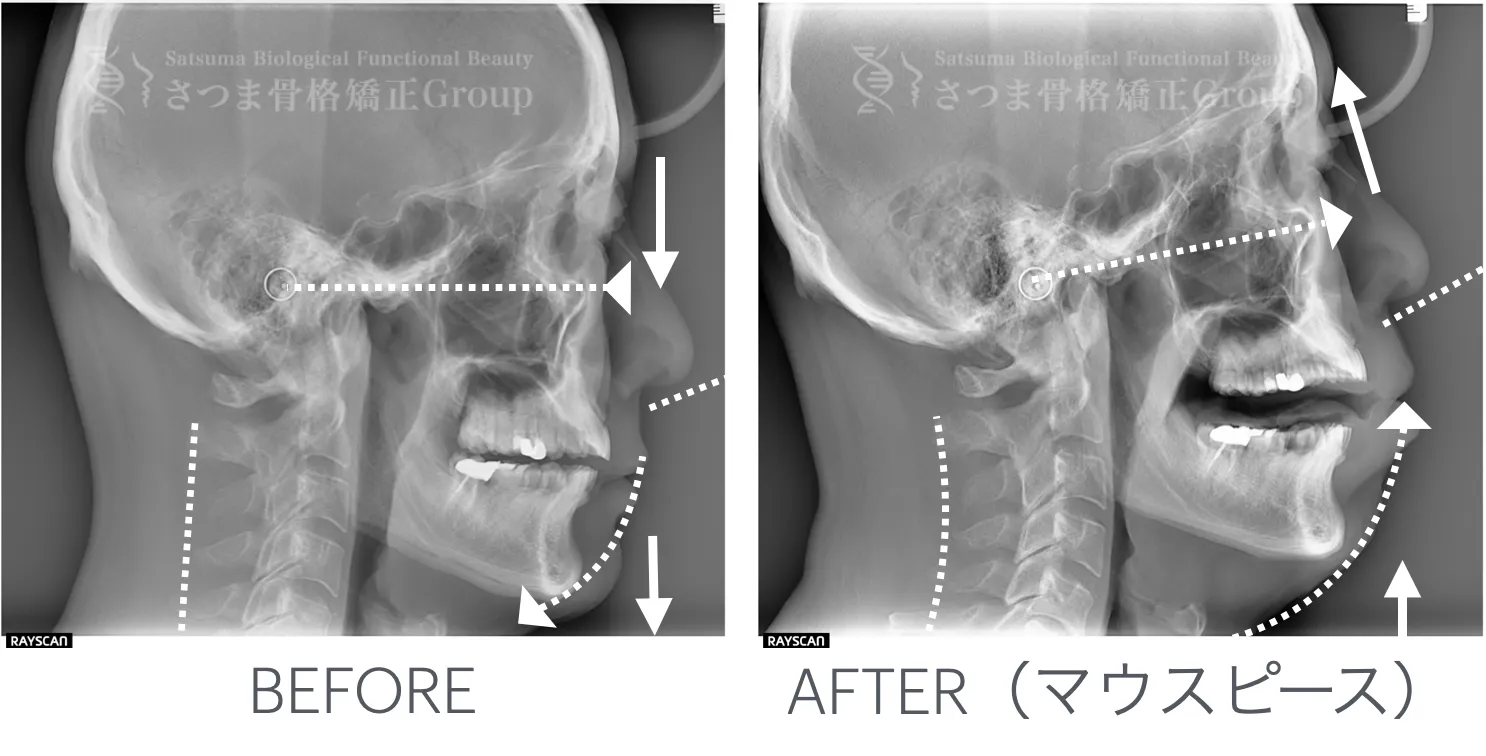

最新のCTスキャンによる顎・顔面・頚椎の立体画像検査を導入。

治療前後の変化を視覚的に確認できるため、

改善のプロセスを“見てわかる”形で効果を実感いただけます。